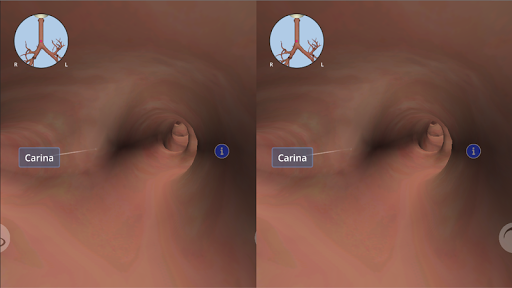

Anatomyou VR to edukacyjna aplikacja mobilna, która prezentuje w sposób wciągający ludzką anatomię.

Korzystając z wirtualnej rzeczywistości, będziesz w stanie poruszać się wzdłuż struktur anatomicznych, stając się częścią ludzkiej anatomii: układu rozrodczego układu krążenia, oddechowego, trawiennego, moczowego, łzowego i żeńskiego.

Anatomyou VR może być używany w dwóch różnych trybach: Virtual Reality i Fullscreen.

W trybie wirtualnej rzeczywistości urządzenie mobilne (smartfon) musi być umieszczone w gadżecie wirtualnej rzeczywistości, aby cieszyć się w pełni wciągającym doświadczeniem. Użytkownik może wchodzić w interakcję z elementami sterującymi nawigacją i elementami informacji anatomicznej, kierując je na cel.

Mimo że zapewnia najlepszą jakość w trybie Virtual Reality, użytkownik może również korzystać z tej aplikacji mobilnej w trybie pełnoekranowym, bez potrzeby korzystania z gadżetu rzeczywistości wirtualnej.

Anatomyou VR może być również używane jako niezwykle przydatne narzędzie do nauczania uczniów w klasie poprzez użycie wirtualnej rzeczywistości (z gadżetami VR) lub trybu pełnoekranowego.